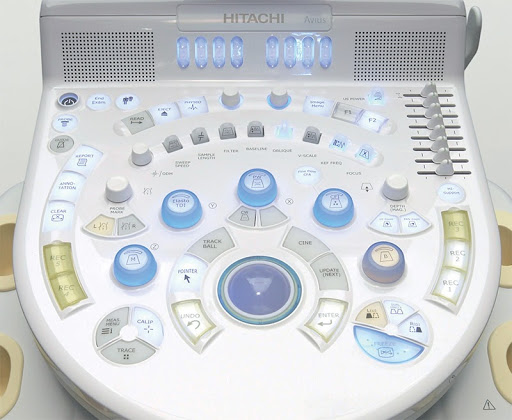

- Эргономичная панель управления с круговым расположением элементов и интерактивной подсветкой клавиш